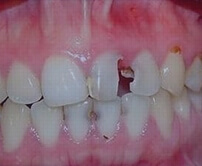

• Exposed pulp pain from a broken tooth.

Broken Crown & Root